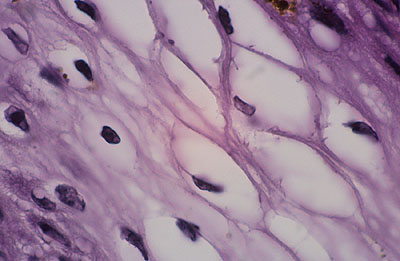

Photo 5 (Hémalun Eosine X 200) : ces crêtes épithéliales tout à fait particulières

(allongées, filiformes, branchues) peuvent également être présentes dans les couches les plus basales

de la gaine épithéliale folliculaire externe des infundibula folliculaires.

On note également l’aspect parakératosique diffus des infundibula folliculaires.

Légendes de la Photo 5 :

- Triangles bleus : contours de crêtes épithéliales allongées, filiformes, ramifiées et branchues, peuplées de cellules basales hyperbasophiles, émanant de la gaine épithéliale externe des infundibula folliculaires

- Flèches rouges : parakératose épidermique et folliculaire

- Étoiles rouge pleines : Le derme est faiblement à modérément inflammatoire (infiltrat mononucléé)

- Étoiles rouge claires : angiectasie des capillaires sanguins

- Ronds marrons : tiges pilaires